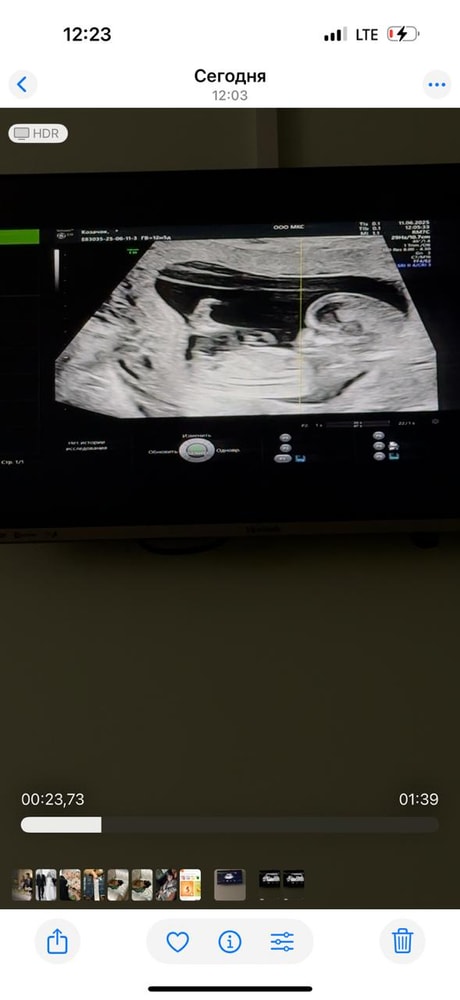

Определение пола по половому бугорку.

Нужен совет (вне обсуждений основной темы сообщества, но в рамках разумного)Всем привет! На первом скрининге сказали 95% девочка, а сегодня была на УЗИ перед отпуском, сказали, что больше похоже на мальчика 😆 Кто умеет определять по половому бугорку?